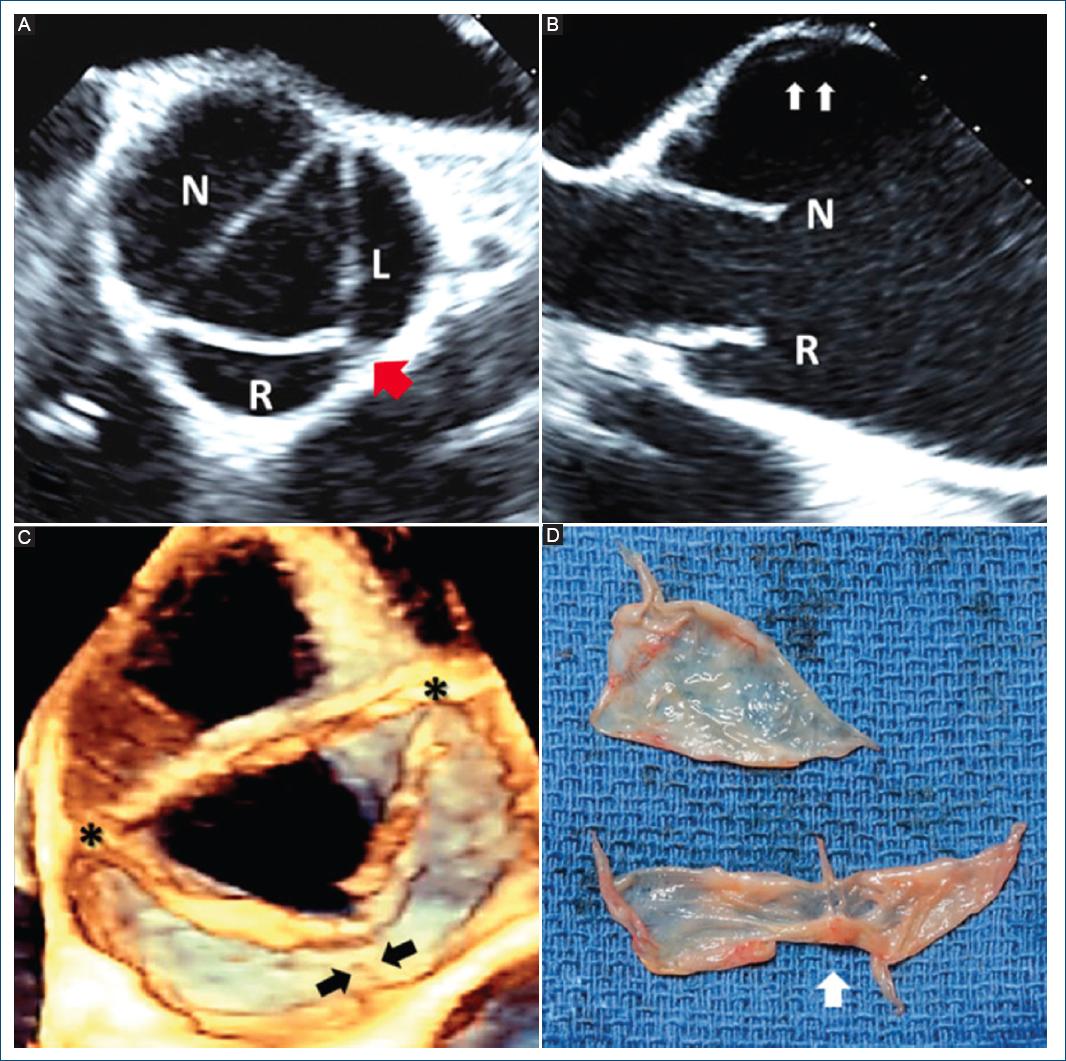

Figura 14 Imágenes sistólicas de ecocardiograma transesofágico y fotografía intraoperatoria de una válvula aórtica bicúspide de fusión parcial. A: el ecocardiograma transesofágico intraoperatorio de dos dimensiones muestra una apertura sistólica triangular con una sospecha de pequeña fusión entre las cúspides derecha (R) e izquierda (L) (flecha roja). B: el eje largo transesofágico bidimensional no muestra evidencia de domo sistólico con dilatación asimétrica del seno no coronario (flechas), que se acompaña de una dilatación significativa de la aorta ascendente en este paciente. C: el eje corto sistólico transesofágico tridimensional muestra un pequeño rafé (flechas) entre las cúspides derecha e izquierda con otras dos comisuras normales (asteriscos). D: la válvula explantada muestra el pequeño rafé entre las cúspides derecha e izquierda (flecha). N: cúspide no coronaria.